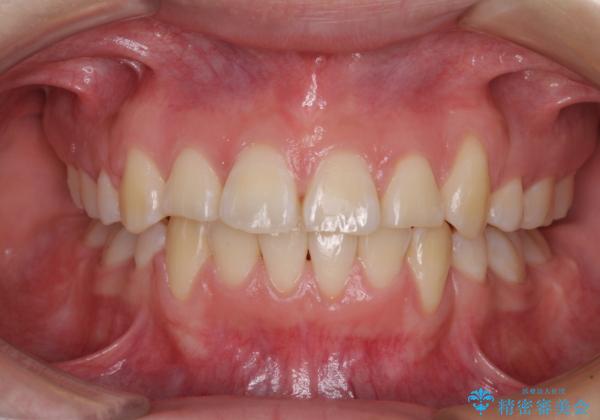

- 上下前歯の叢生と八重歯を気にして来院された患者様です。

前歯部叢生のスペースを獲得するため、上下顎左右小臼歯各1歯を抜歯することとしました。

歯列はきれいに整いますが、歯肉ラインは治療前の歯肉の位置を踏襲します。

特に八重歯であった歯は歯冠が長く見えますので、改善を希望される場合には、歯肉移植術を行う必要があります。